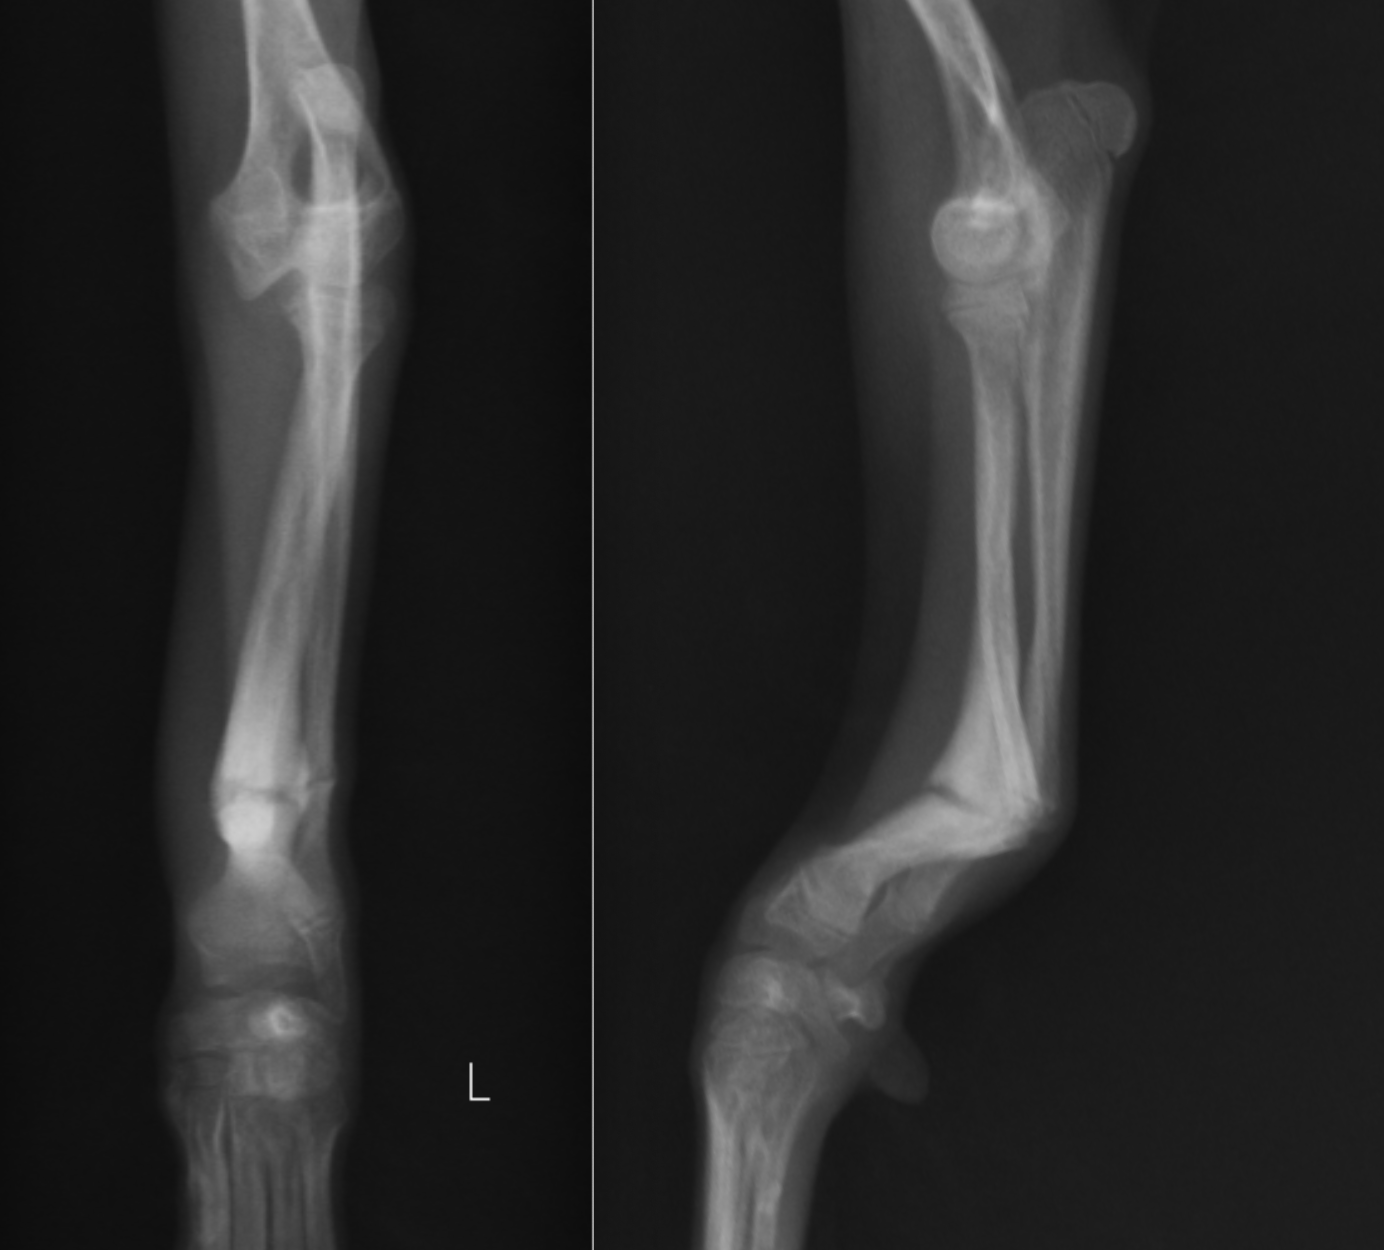

前肢・橈尺骨矯正骨切り術

今回は1ヶ月ほど前に足を痛がっていたそうですが、しばらくすると痛みがなくなったので様子を見ていたら、曲がったままになってしまったということで来院されたトイプードルを紹介します。

橈尺骨が曲がっているのが分かると思います。この子は、この状態で足を杖のようにしてバランスを取るのに使っていましたが、通常のように負重することはできませんでした。

肉眼的にもかなり湾曲しているのがわかります。

このように曲がったままの状態ですと、うまく足を使えないのはもちろん、何らかの拍子で力が加わったときに曲がった部分で骨折する可能性が高いです(応力集中)。

治療をする場合には細かい計画を立て(角度や長さを術前から計画する)、一度人工的に骨切りを行い、可能な限り真っ直ぐにしてからプレート固定します。一番右が術前、真ん中が術後、左はプレート抜去後になります。